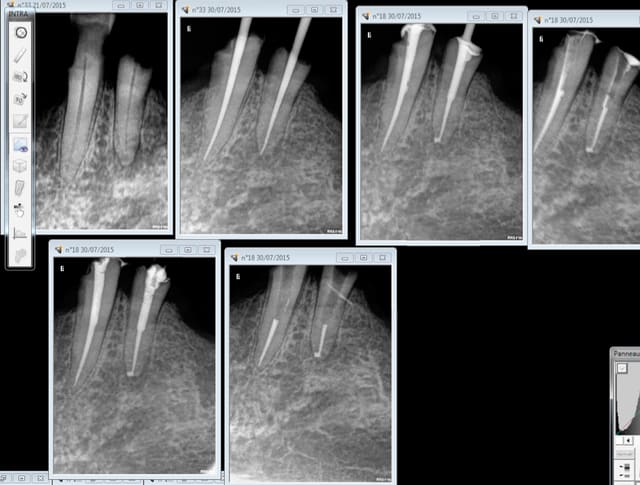

Ca c'est pas mal non plus en 45 mn, on se demande pourquoi thermo compacer au mac spadden et j'ai perdu un morceau de crochet au passage ! -)))))

Endo 16 + sc 33. Costeaude la racine DV.

Ca m'arrive de foirer mais rarement, ici racine distale de 16 manque 2 mm. je n'essaie pas de forcer outre mesure et d'arriver à tout prix à l'apex.

Il y a parfois des casses de pointes de Mc Spadden comme sur la radio de la 14 mais comme c'est un instrument stérile noyé dans de la gutta ça ne (me) pose pas de problème.